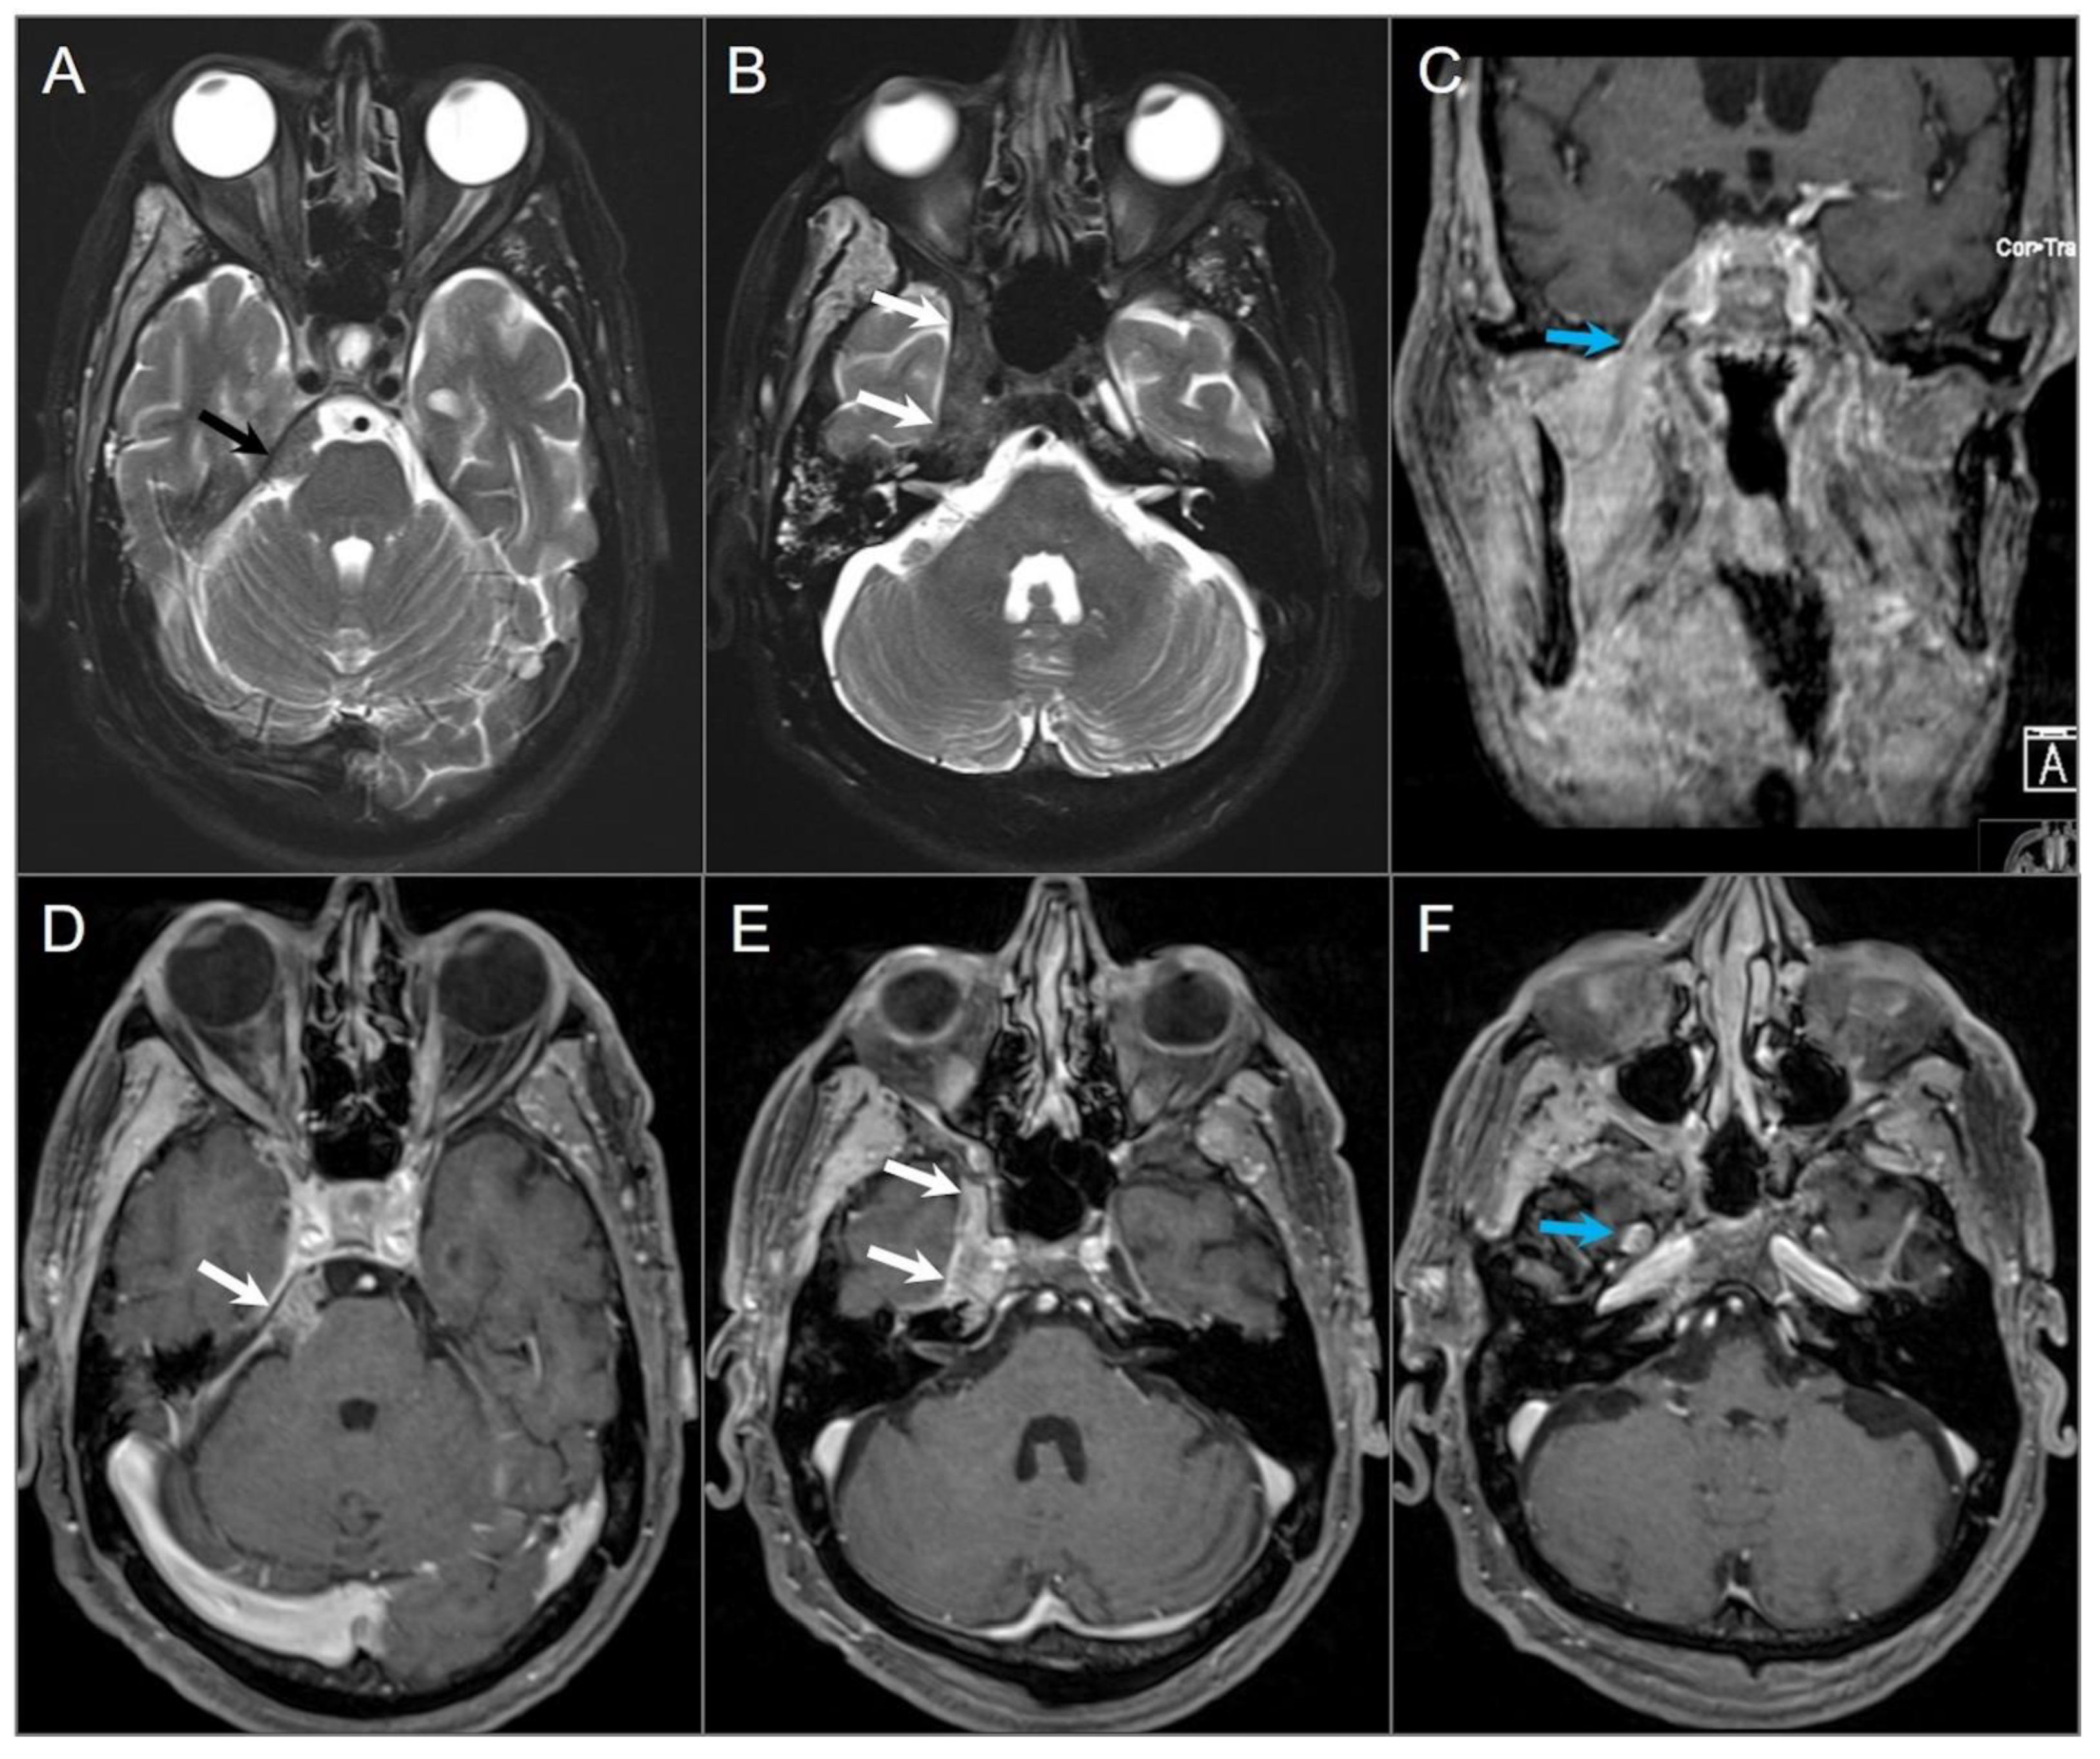

4.1.2. Schwannoma